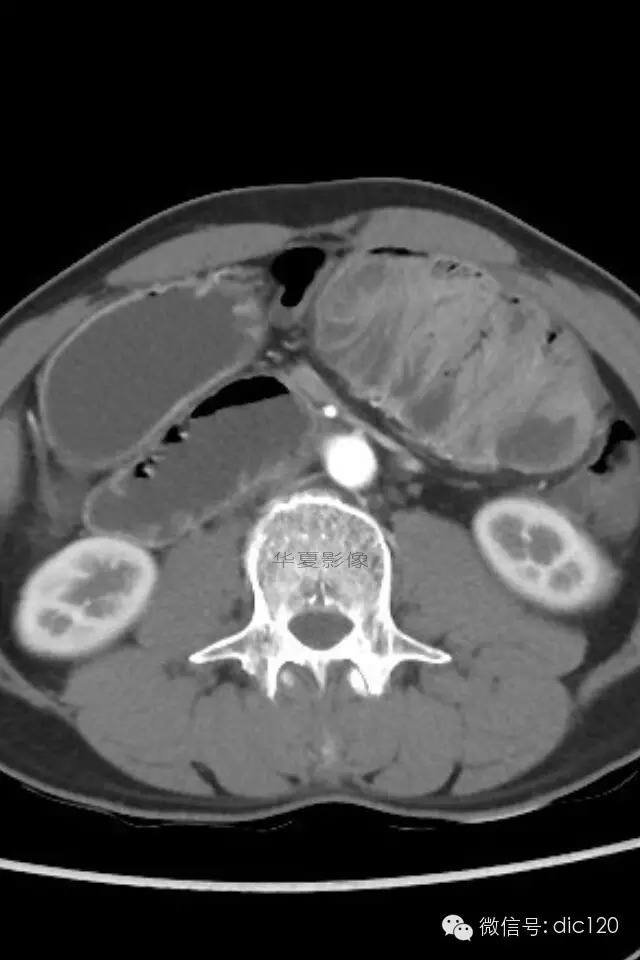

肠茧症,即小肠茧状包裹症,又名:腹茧症,先天性小肠禁锢症。多为先天性畸形。

腹茧症以小肠被茧状包裹在一层异常的纤维膜内为其特征,为一种少见的,原因不明的特殊类型的肠梗阻。包膜厚薄不均,增厚处呈乳白色,包膜内小肠间或包膜间可有疏松粘连,包膜可局部增厚,形成缩窄环或束带压迫肠管形成梗阻,肠梗阻发生率约为57%,腹茧症伴腹腔内畸形率较高,约为54%。腹茧症92%的病人以肠梗阻就医,其中亚急性肠梗阻和慢性肠梗阻占71%,一些病人是在腹部手术时偶然发现本病。腹茧症女性多见,Francis总结以下情况可想到本病:1.青年女性,有不明原因的肠梗阻。2.既往又类似发作史,可自行缓解。3.常表现为腹痛及呕吐,但缺乏肠梗阻的四大典型症状。4.触诊腹部有无压痛的包块,质地软。腹茧症治疗以手术为主,充分松解粘连缩窄环,彻底解除梗阻使小肠复位或加以肠排列等。绝大多数病人术后症状消失,少数病人遗留症状,可试服用泼尼松,维生素B1治疗。

肠茧症分为两种类型:

1.单层包裹型 由单层纤维组织膜将小肠或其它脏器包裹。此种类型常包裹小肠及其系膜。手术时进腹容易,容易发生肠梗阻。

2.多层包裹型 俗称“千层饼”样包裹,其纤维层次多而广泛。手术时进腹困难,被包裹的脏器无移动性,发生肠梗阻的机会少。